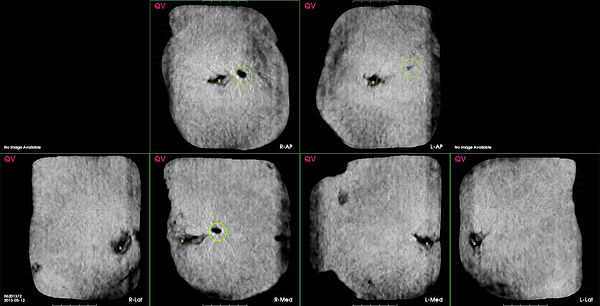

- A QVCAD Navigator image of all ABUS volumes in the study presented in a coronal image format as seen below where CAD has detected possible abnormalities. CAD marks are presented as colored green circles around areas of interest and displayed over the CAD Navigator image. CAD marks are intended to highlight potentially malignant lesions.